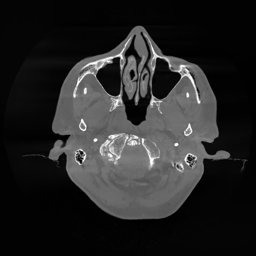

III-D Real Clinical Data Experiment

The experimental results on clinical head data are shown in Fig. 4. The reference images were reconstructed using the fast iterative shrinkage-thresholding algorithm (FISTA) with total variation regularization from non-truncated projection data. In the WCE reconstructions (Fig. 4(b)), severe truncation prevents accurate recovery of anatomical structures outside the FOV. Despite being trained solely on simulated data with a domain gap, all deep learning models can restore a substantial portion of the missing anatomy. Among them, the diffusion-based methods recover soft-tissue boundaries more faithfully than the conventional deep learning approach FBPConvNet, highlighting their stronger image generation capability. However, cDDPM reconstructions exhibit more noticeable noise than those from other methods, consistent with the simulated data results. The patchDiffusion model introduces artifacts within the FOV, likely due to its patch-wise processing strategy. While I2SB shares the same limitations as other diffusion models in perfectly restoring soft-tissue detail, it produces fewer residual noise patterns and fewer artifacts within the FOV boundaries. Overall, Fig. 4 demonstrates the strong efficacy of I2SB in reconstructing real CBCT data.